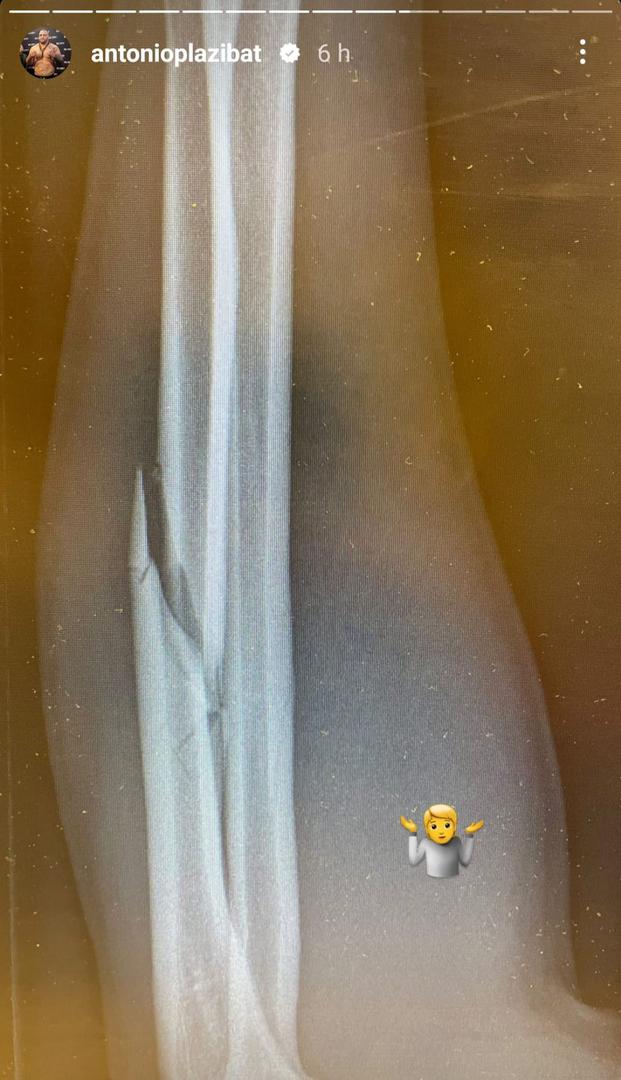

FOTO Plazibat objavio rendgensku snimku slomljene ruke i otkrio da mora na operaciju

A jedan je svakako slomljena desna podlatkica već u prvoj rundi. Malo je boraca koji bi nakon takve ozljede nastavilo borbu ali Plazibat nije htio odustati. Nastavio se boriti bez svog najjačeg oružja i izgubio i to tako da se na koncu predao. Naime, kad ga je Osaro stisnuo uz konopce, u kojoj kanonadi je koristio i koljena, Plazibat je završio na podu ni ne pokušavši ustati. Na upit suca, samo je odmahnuo glavom, shvatio je da dalje nema smisla, i borba je prekinuta.

Poslije borbe objavio je na svom Instagram profllu snimku s rendgena koja otkriva da mu je slomljena ruka i trebat će na operaciju kako bi se sanirala ozljeda.

- Slomljena mi je podlaktica, vanjski dio podlaktice. Trebat će operirati, sve je drugo je dobro. Barem sam prvi borac koji je uspio nokautirati suca - rekao je hrvatski borac.

Foto: Instagram Antonio Plazibat